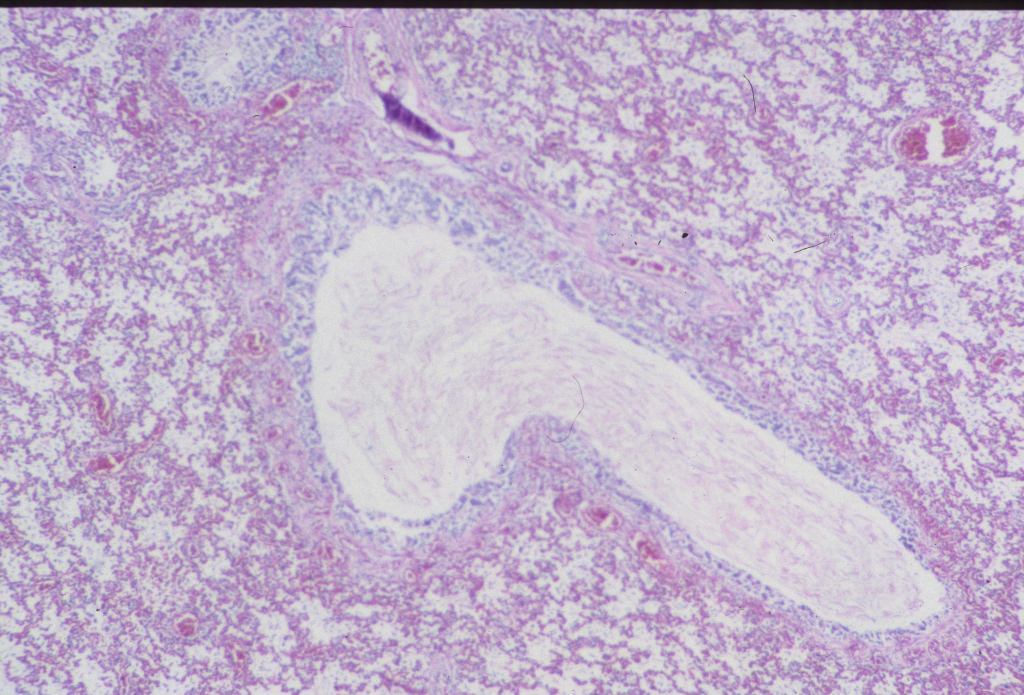

Pulmonary hyperplasia: The complete obstruction of the larynx or trachea paradoxically increases intrapulmonary pressure by occluding the egress of pulmonary secretions from the lung. This elevated pressure stimulates increased, although morphologically distorted, lung growth, and hence heavy lungs (Fig 6 a, b).